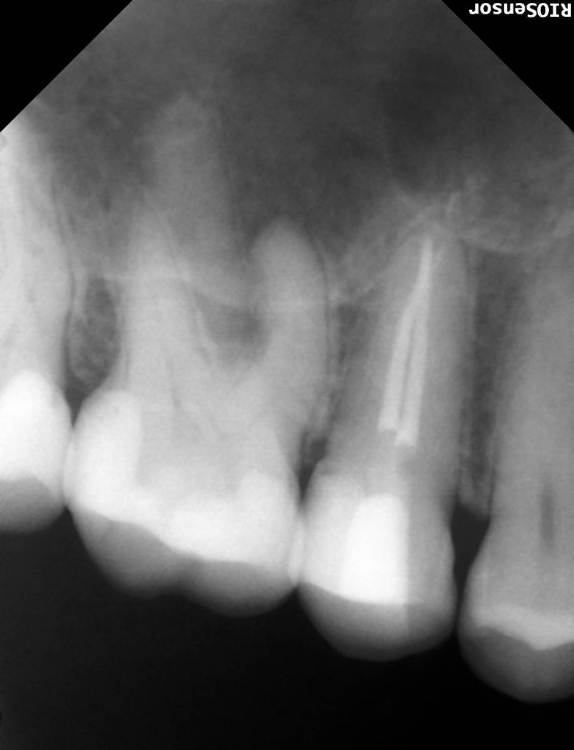

Александра117 Опубликовано 19 ноября, 2022 Поделиться Опубликовано 19 ноября, 2022 Всем Привет! Месяц назад лечила зуб верхнюю 5ку. Депульпировали и Пломбировали каналы гуттаперчей. На момент лечения в зубе уже была боль. Был поставлен диагноз пульпит. Но прошел уже месяц и боль в зубе сохраняется , при этом почти точно такая же как и до лечения. Боль постоянная ноющая средней интенсивности. Я думала это первое время после лечения такая боль будет. Но месяц прошел, а боль не уходит. Немного предыстории этого зуба: Зуб этот меня вообще не беспокоил изначально. Я пришла 12.09.2022 на прием, чтобы вылечить кариес. Стоматолог рассверлил и запломбировал. Но сказал, что очень глубокий кариес был, но решил пока сохранить пульпу и наблюдать. После лечения появились боли в зубе ,но терпимые. Через две недели боли усилились. Я пришла на прием снова с этим вопросом. Врач сказал, что после лечения глубокого кариеса могут быть боли, надо ещё понаблюдать. Ещё через пару неделю боль не проходила. Была довольно сильной. Врач принял решение депульпировать зуб. Лечение я проходила под микроскопом у опытного эндодонтиста. Именно у него я уже до этого лечила каналы у нескольких других зубов, и все было нормально. Но также это в в первый раз такое случилось, что боли такие сохраняются в течение месяца после лечения. После лечения врач сказал, что зуб меня беспокоить не должен больше. Сказал, что было лечение неосложненного пульпита. Но он беспокоит вот уже месяц. Вообще это у меня впервые, чтобы была боль в зубе и на момент лечения и после лечения каналов. До этого до болей в зубе дело не доходило. Пролечивалось раньше. Сделала свежие снимки Рентен через месяц после Лечения, их прилагаю сюда. По снимку видно, что каналы пройдены полностью до конца. Материал за Пределы Корня не выведен. Найдены все каналы. Их у меня в верхних пятерках их по два. Как и видно по КТ. Скажите, что это может быть? И что Можно сделать? Требует ли эта ситуация какого то срочного вмешательства или можно ещё наблюдать? Может ли это быть периодонтит, при том что на снимке в прикорневых тканях все спокойно? Ещё на внешней стороне зуба есть две белые трещины. Как раз на границе пломбы и стенки Зуба. В этом месте если трогать языком очень шершавая поверхность. Также, можете сказать, эти трещины это трещины Эмали или может быть что и более глубокие Трещины? ( Фото трещин тоже прилагаю) Ссылка на комментарий

Doc Опубликовано 19 ноября, 2022 Поделиться Опубликовано 19 ноября, 2022 А какого характера боли? Самопроизвольные, на холодное-горячее, острые или не очень, ночные-дневные, длительные или кратковременные? Это может иметь диагностическую ценность. Между пятеркой и шестеркой на снимке есть подозрение на кариес корня, но по этим снимкам сложно сказать что-то определенное. Ссылка на комментарий

Doc Опубликовано 20 ноября, 2022 Поделиться Опубликовано 20 ноября, 2022 На пятерке почти точно, на шестерке сложно сказать по этому снимку, но подозрение есть тоже. Если там есть кариес корня, то он вполне может перейти в пульпит и так болеть. Ссылка на комментарий